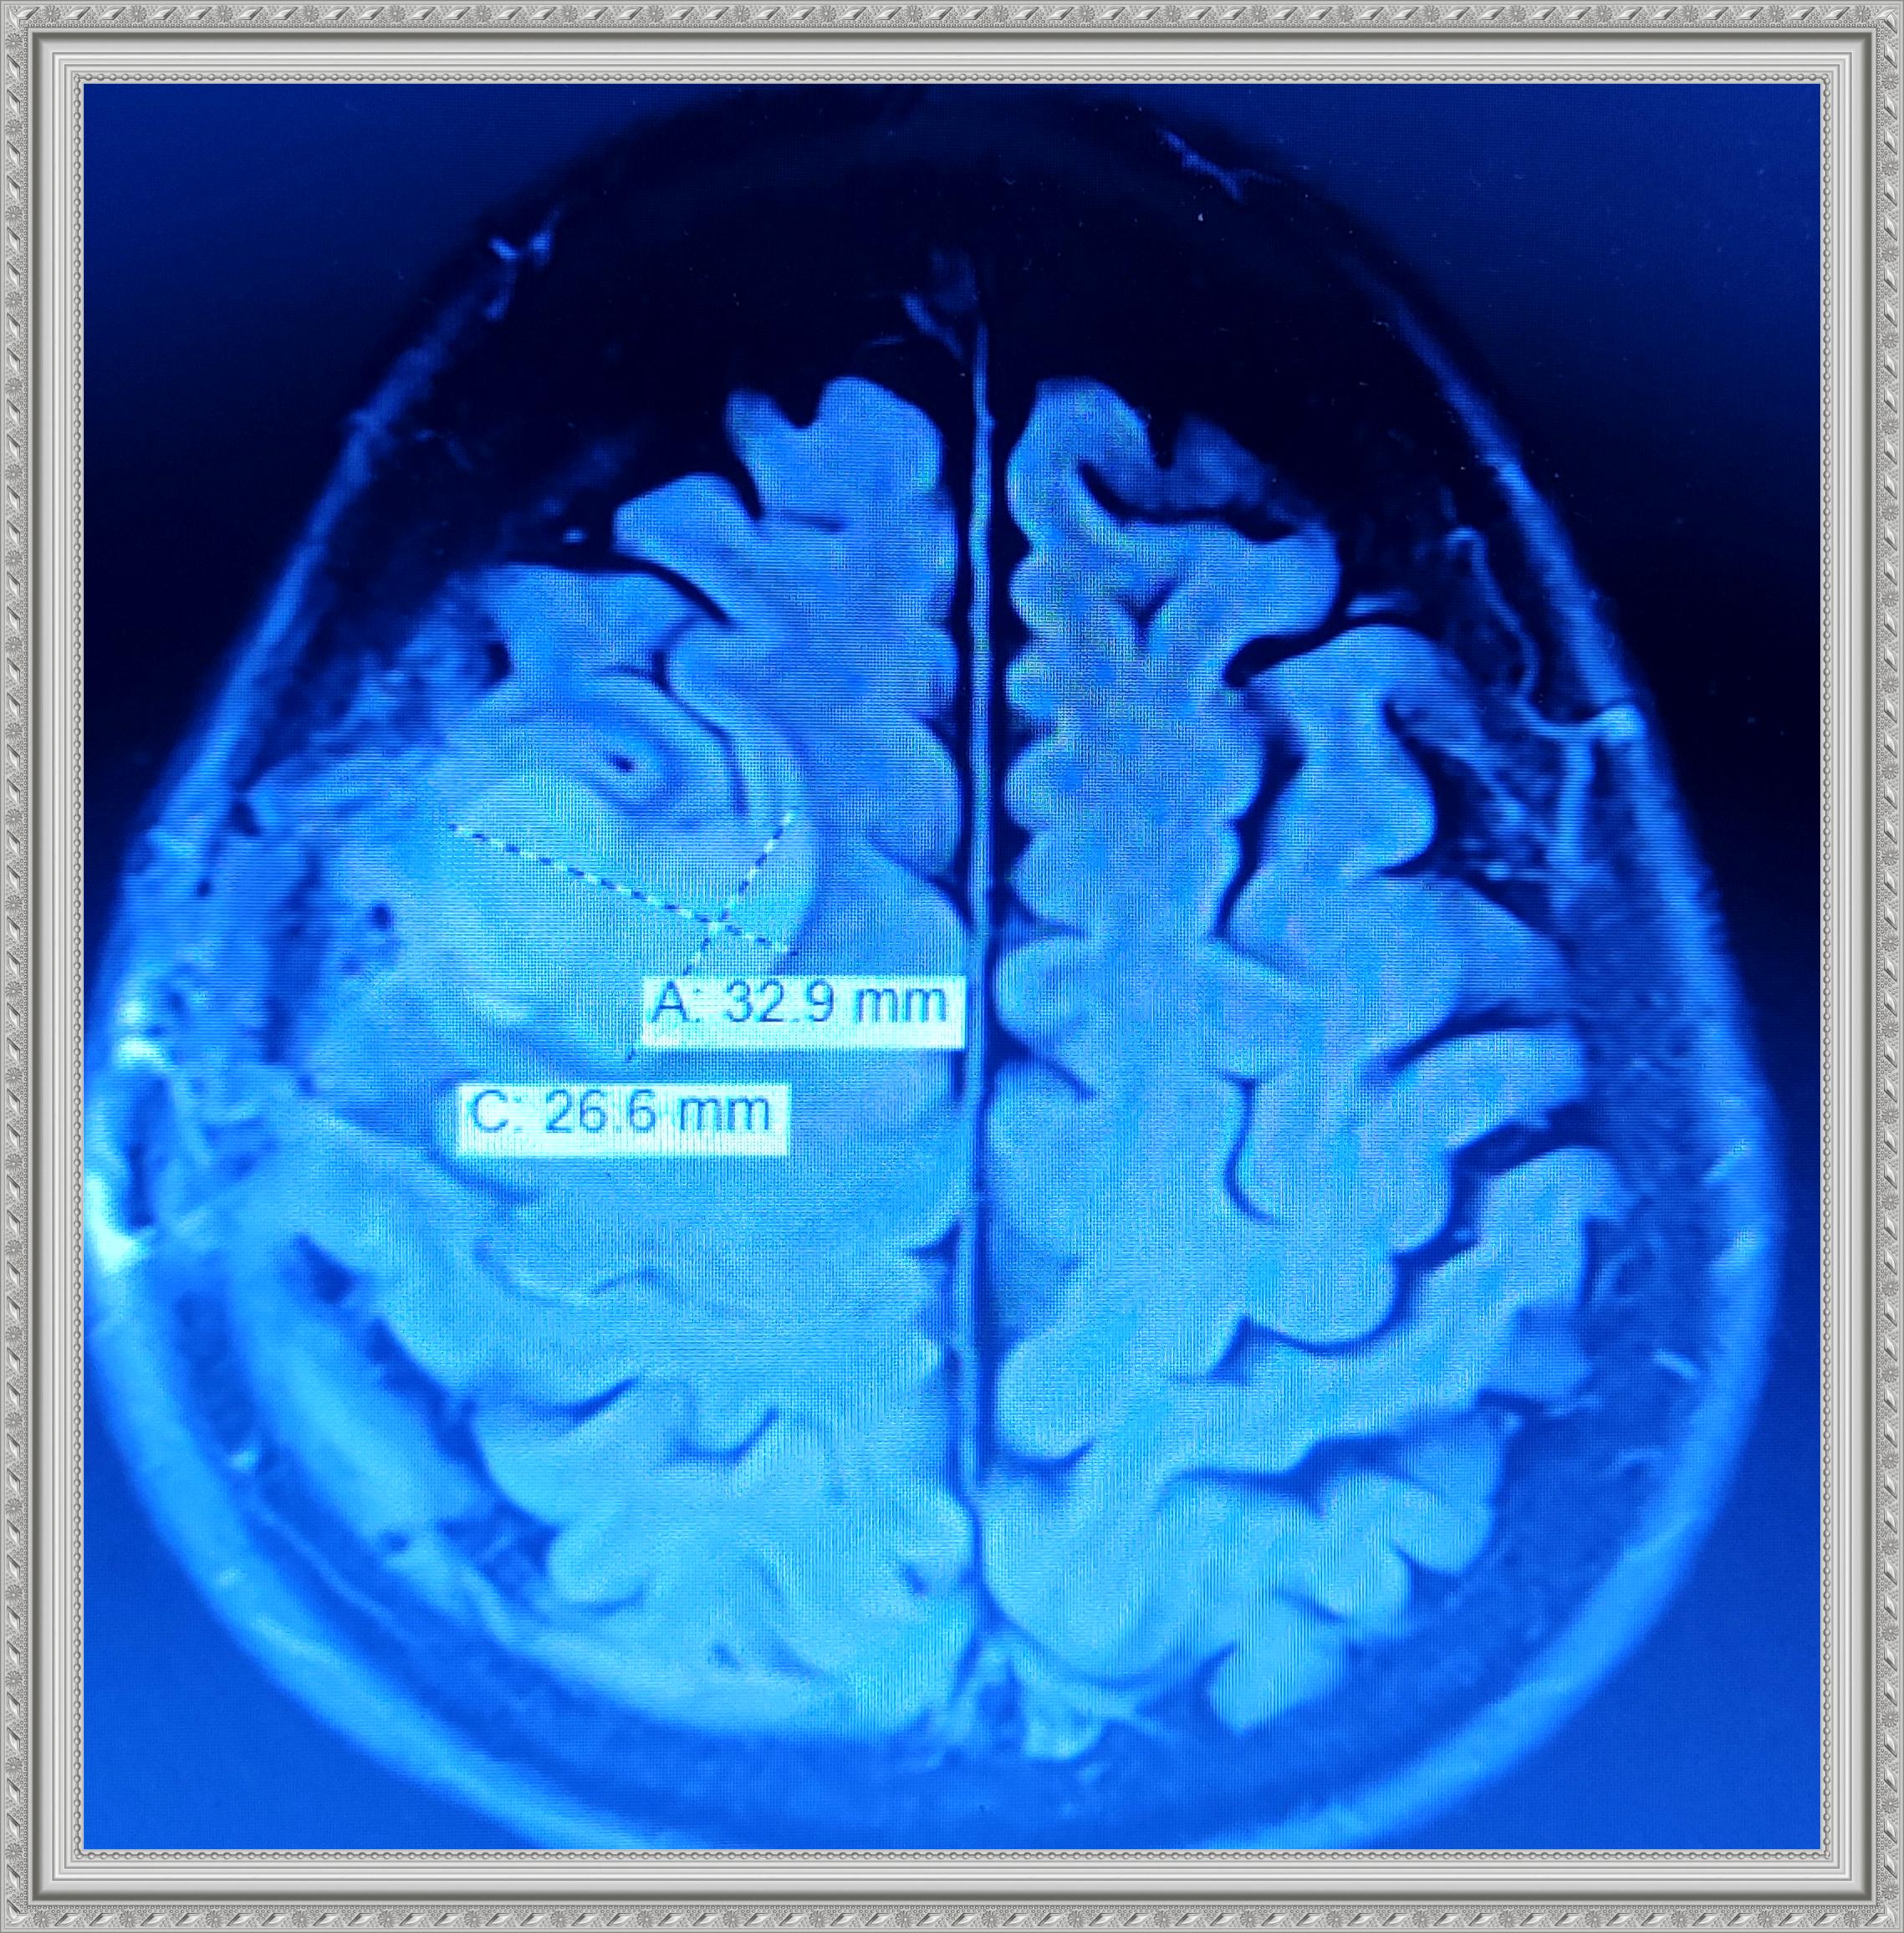

The next gallery shows me at Memorial Central Hospital in Colorado Springs after having surgery to remove my tumor and staying for a few weeks after for Physical, Speech and Occupational Therapy. The staff there was so AWESOME! I hold every one of them dear to my heart.